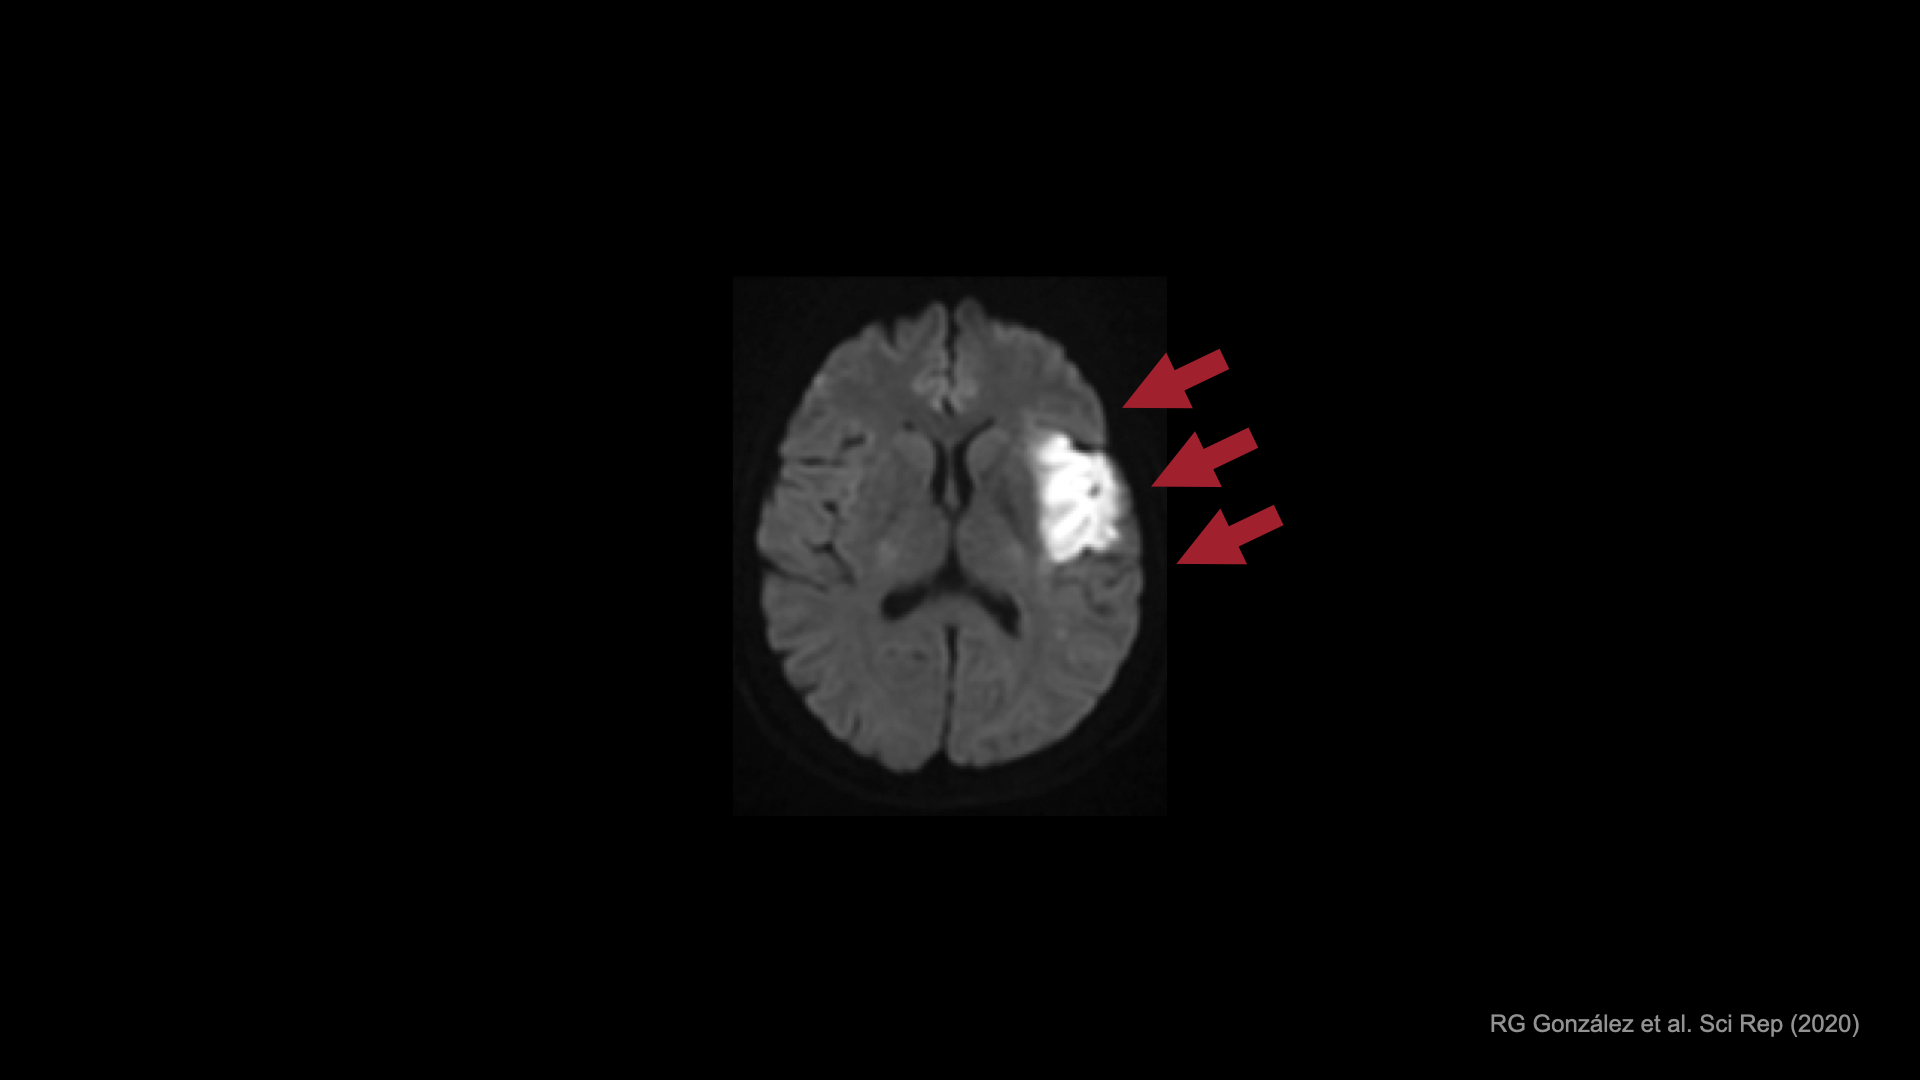

こちらは、脳卒中患者のMRI画像です。

運動機能を司る領域が深刻なダメージを受けたことで、手には重度の麻痺が残ってしまいました。

こちらは、重度症例のMRI画像です。

麻痺している右手を動かそうとしても、運動の生成に必要な運動野には活動が見られません。

しかし、1日40分の訓練をたった10日間続けることで、運動野の活動が新たに出現することが分かりました。